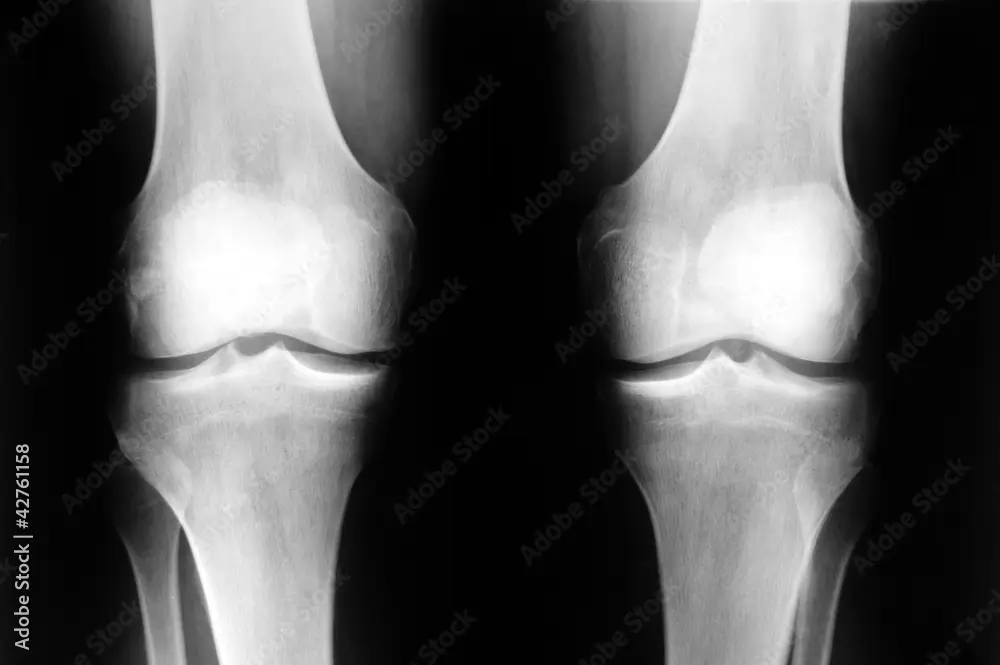

Les douleurs de genou peuvent résulter de divers facteurs tels que des blessures, des déséquilibres posturaux ou des troubles biomécaniques. En podologie, nous cherchons à comprendre l'origine de la douleur pour mieux la traiter.

Le podologue évalue la posture et la marche du patient pour détecter d'éventuels déséquilibres pouvant provoquer des douleurs au genou. Par l'utilisation d'orthèses et de traitements spécifiques, il aide à corriger ces problèmes et soulager la douleur à long terme.